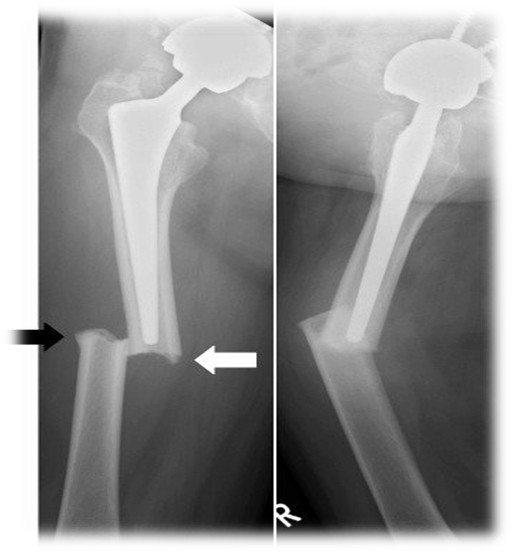

rzedstawiony radiogram wskazuje na złamanie okołoprotezowe typu: